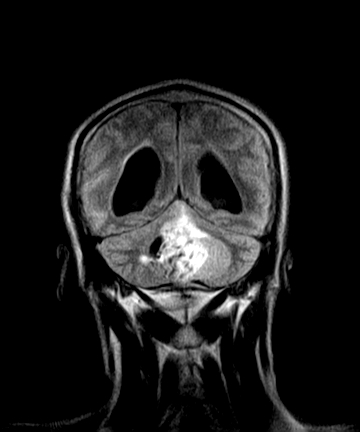

四脑室区见混杂信号占位影,脑室系统扩张明显,临近结构显著受压称位,患者52岁,多考虑室管膜瘤可能性大

考虑第四脑室室管膜瘤并阻塞性脑积水。

定位;脑室内富血供占位

1,脑室内血管母细胞瘤。

应该是来源于小脑蚓部的占位,如血管母细瘤或星形细胞瘤

考虑第四脑室室管膜瘤【血供丰富血管母细胞瘤可能】并梗阻性脑积水;部分性空蝶鞍;左侧上颌窦粘膜下囊肿。

小脑蚓部胶质脑膜瘤突入四脑室;肿瘤内见血管流空信号和钙化信号.

比较典型的脉络丛乳头状瘤并脑积水,鉴别小脑蚓部血管母细胞瘤。